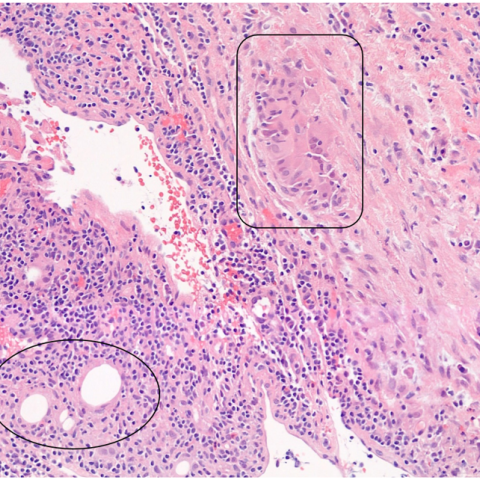

结果:腋窝淋巴结脂肪浸润。

9a209bfa122b6920704aa5ad2f09a5f5.pngd959577af5abcb3b584853407685a39d.png

至今尚无研究报告显示腋窝淋巴结在自体脂肪移植(AFT)后出现脂肪浸润。然而,我们的病例通过病理学确认了这一现象。影像学发现显示这些脂肪沉积在 T1 加权 MRI 图像上表现为小的脂肪衰减区域,而在超声检查中则表现为脂肪回声。

研究表明,腋窝淋巴途径是乳腺组织的主要引流途径,淋巴液直接引导或通过Sappey丛的网络运输到腋窝。在不同情况下都观察到了细胞或颗粒通过淋巴通道的迁移,这表明通过自体脂肪移植引入的脂肪细胞可能会沿着这些既定的淋巴通路移动。这为脂肪及其吞噬细胞沉积在腋窝淋巴结中的存在提供了一个合理的机制,这一点得到了我们的影像学和病理学的证实。